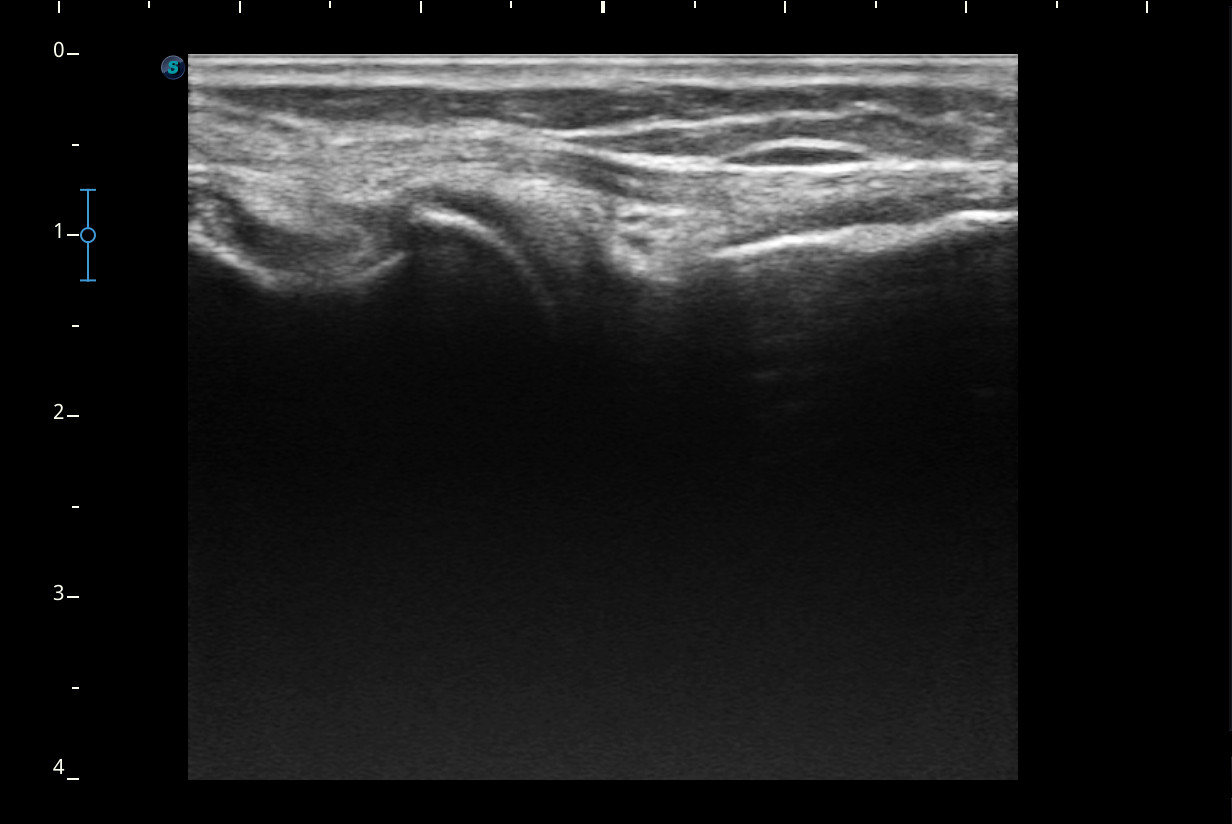

Descripción de los hallazgos ecográficos y las imágenes más relevantes para la resolución del caso

Rodilla sin derrame articular. No se aprecian lesiones en Ligamentos colaterales. Ligamento rotuliano sin hallazgos valorables. Rotura menisco interno y dudosa fisura menisco externo. Tendones rotuliano y cuadricipital normales.